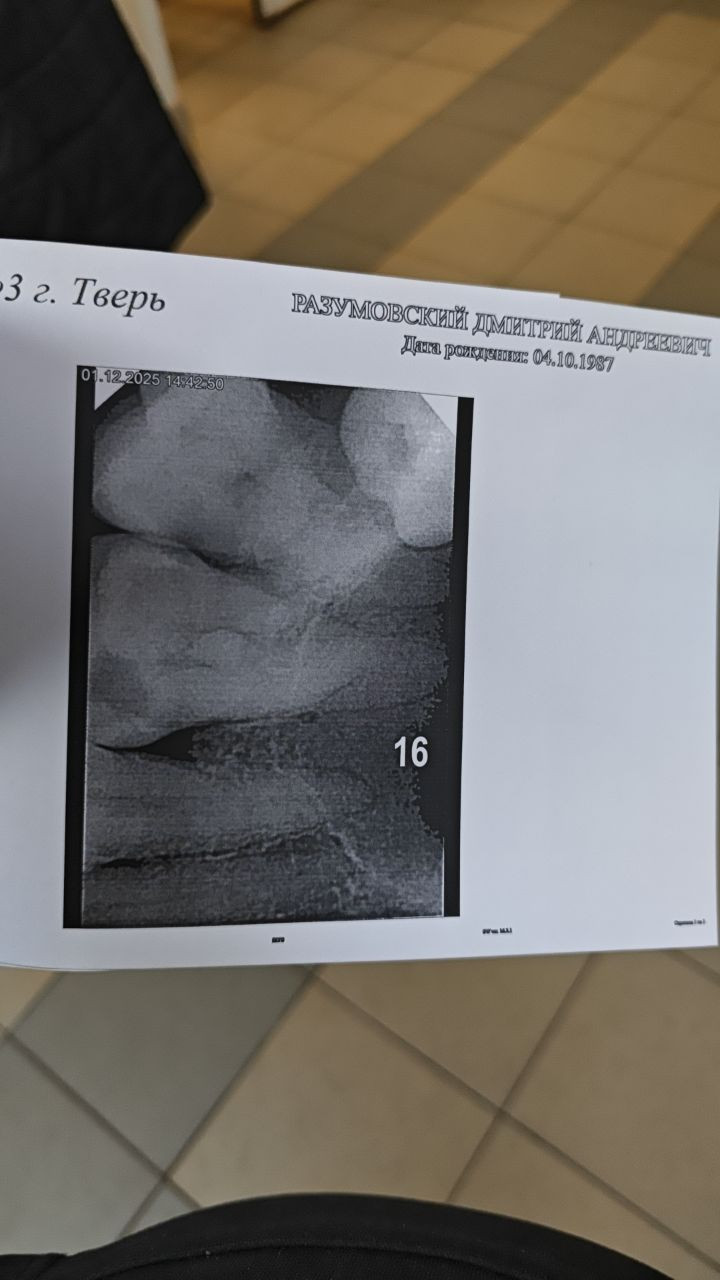

Добрый вечер, вчера пришёл к стоматологу, с болью в 16 верхнем зубе, сделали снимок, потом расверлили зуб, положили туда мышьяк, сделали временную пломбу, сказали приходи через 10 дней, я приехал домой, поел и лёг спать, сегодня проснулся в 6 утра от боли в зубе, которая расходится и на нижние зубы тоже, иногда и на висок, выпил найз, он помог минут на 30, боль то нарастает, то утихает, что делать не знаю, очень сильно болит